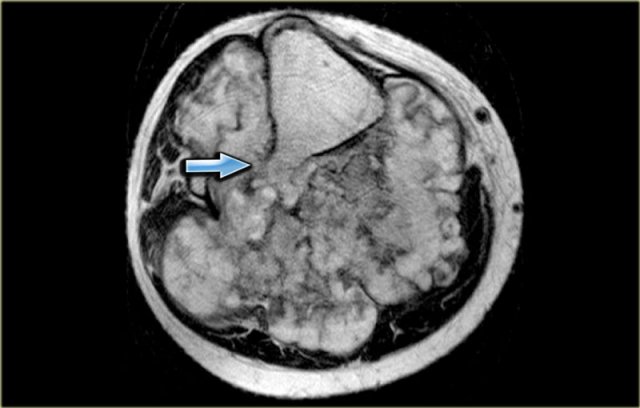

Chondrosarcoma (8) continued

On the left the axial T2 WI.

Notice that the tumor arises from an osteochondroma, which is shown in the center part of the image (arrow).